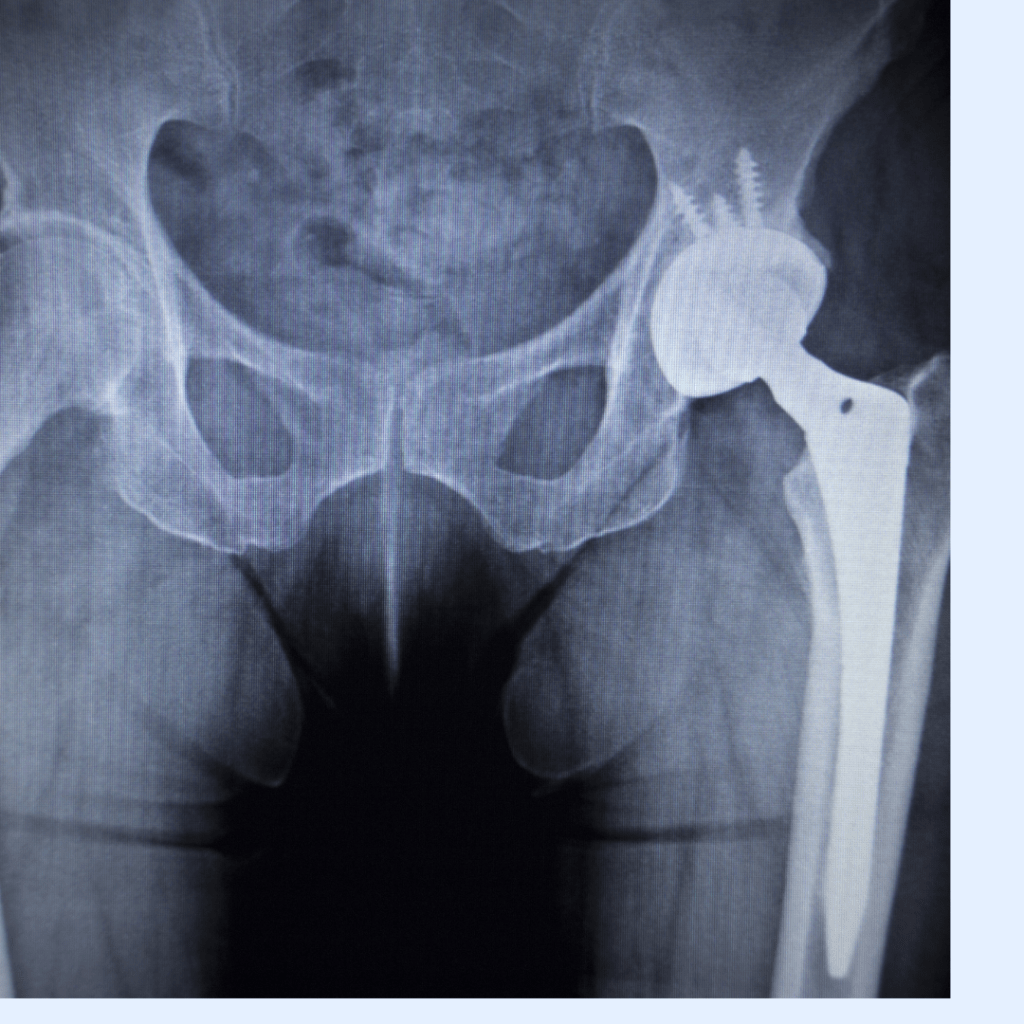

- Cerrahi Müdahale: Diğer tedavi yöntemleri etkili olmadığında veya kalça eklemi ciddi şekilde hasar gördüğünde, kalça eklemi protezi ameliyatı düşünülebilir.